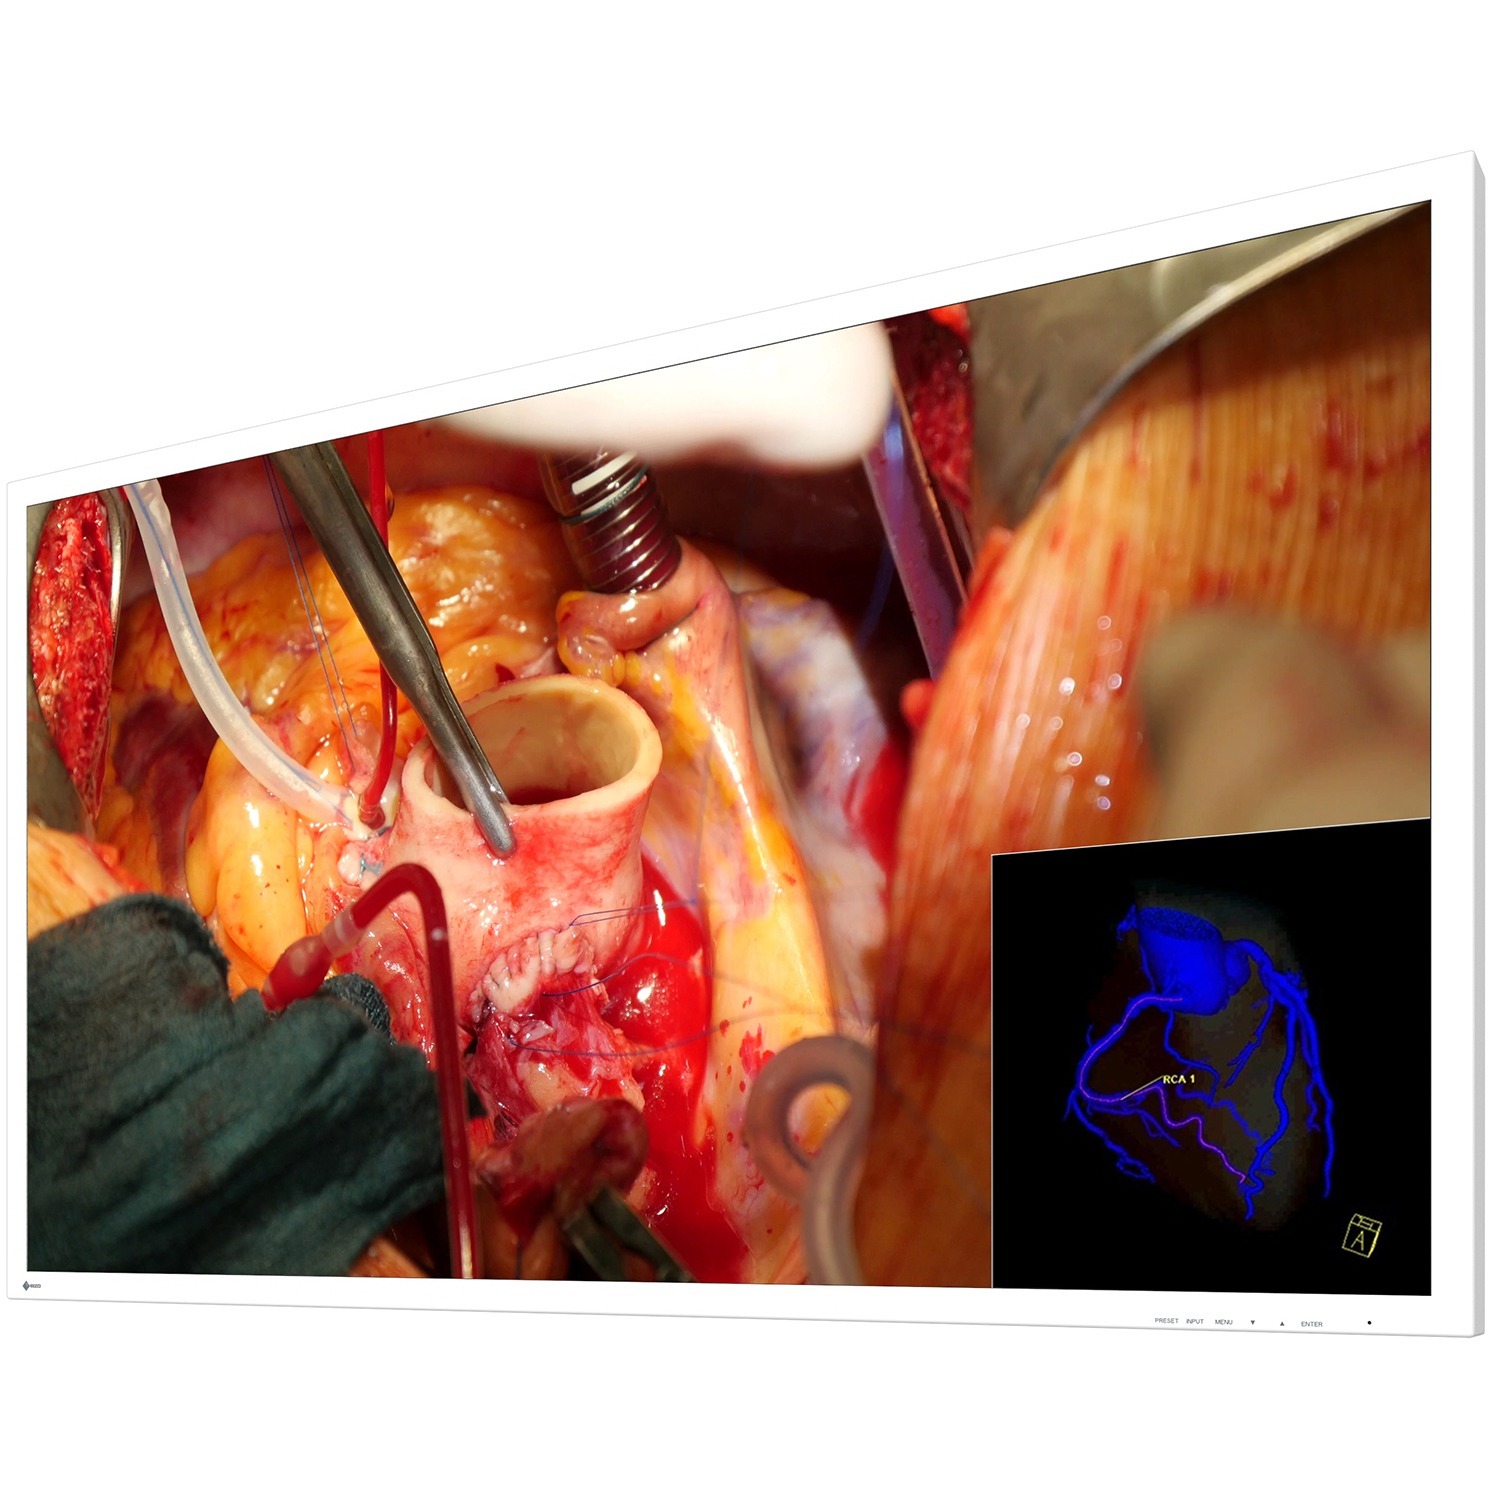

Viewing Multiple Signals on One Screen

In dual source mode, two separate signal sources can be viewed simultaneously on one monitor screen side-by-side using the PaP (Picture-and-Picture) function. With the PiP (Picture-in-Picture) function a second signal can be displayed above the main signal. The size and position of the display window is adjustable when using PiP. In triple source mode, three signal sources can be displayed on the monitor screen, representing a third signal above two signals displayed side-by-side. This is useful when several images need to be viewed at once such as multiple modalities.

If multipe signal sources are simultaneously displayed on the monitor, each image's display mode (e.g. Gamma or DICOM) can be adjusted without affecting the presentation of the other image. This is perfect for multi-modality use, when endoscope, CT or MRI images are accurately displayed on the monitor.